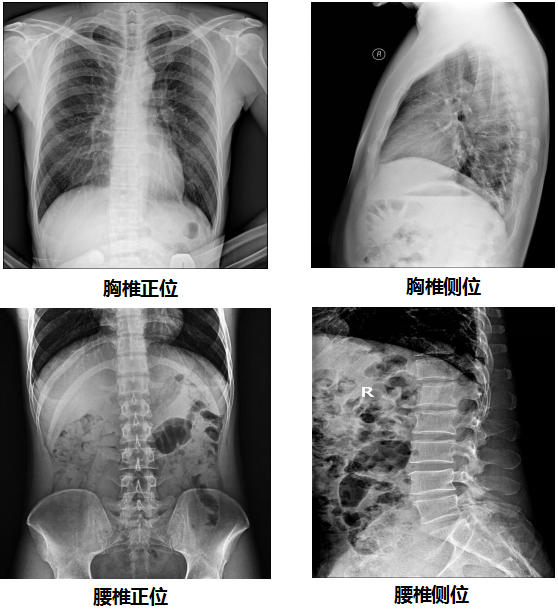

【U直臂DR部分臨床效果圖】